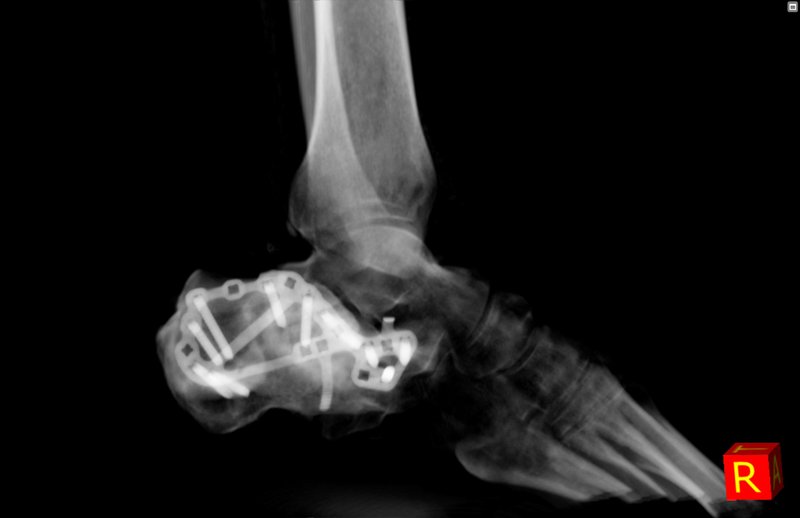

Mit fortschrittlichen Funktionen zur automatischen Anpassung von FOV und Röntgendosis an den Körperbau des Patienten optimiert Newtom 7G jede Untersuchung, sowohl im 2D- als auch im 3D-Modus. Die Dual-Energy-Technologie verbessert die diagnostischen Leistungen noch weiter und ermöglicht die Gewebecharakterisierung, die Reduzierung von Metallartefakten und die Erstellung monochromer virtueller Bilder für eine immer genauere Diagnose.

In einem einzigen Gerät finden Radiologen und Fachärzte die ideale Lösung für eingehende Untersuchungen an Knochen- und Weichgewebe, was sowohl die Diagnosephase als auch die postoperative Nachsorge verbessert.

Dieser innovative Ansatz ermöglicht die Charakterisierung der chemischen Zusammensetzung von Geweben und verbessert die Unterscheidung zwischen kortikalem Knochen, trabekulärem Knochen und Weichgewebe.

Quantitative Tests zeigen eine deutliche Verbesserung der HU-Genauigkeit, der Kontrastauflösung und der Bildhomogenität im Vergleich zu Single-Energy-Untersuchungen. Darüber hinaus korrigieren fortschrittliche Algorithmen automatisch Bewegungsartefakte und gewährleisten so auch unter schwierigen Bedingungen eine hervorragende Qualität der Bilder.

Dank der speziellen Software können die Energiestufen in Echtzeit ausgewählt werden, um detaillierte und maßgeschneiderte Informationen während der Anzeige zu erhalten. Virtuelle monochrome Bilder (VMI) und farbkodierte Bilder (Colour-coded images) erleichtern die Segmentierung von Gewebe und die schnelle Identifizierung von Pathologien.